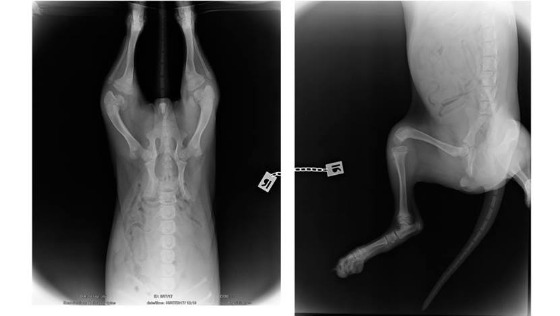

Abi cierpi na obustronne zwichnięcie rzepek do przyśrodka IV stopnia i nie ma możliwości żeby w tym momencie nawichnąć je do pozycji prawidłowej. Konieczne jest wykonanie skomplikwanych operacji obu kolan. Zabieg naprawczy w tym przypadku jest bardzo trudny..

Będzie on obejmował utworzenie rowka bloczka, przecięcie skróconego więzadła pobocznego przyśrodkowego rzepki, wytworzenie nowego więzadła pobocznego bocznego, a przede wszystkim usytuowanie guzowatości piszczelowej w miejscu prawidłowym, co będzie tym samym zlikwidowaniem przyczyny całego tego stanu. Trudność polega na tym że odcięcie i przesunięcie guzowatości piszczelowej może okazać się niewystarczające. Wtedy konieczne będą bardziej zaawansowane zabiegi osteotomii korekcyjnej. Podjęcie działań chirurgicznych musi być natychmiastowe, gdyż wraz ze wzrostem deformacje pogłębiają się. Prawdopodobnie Abi czeka seria zabiegów oraz długi okres rehabilitacji..